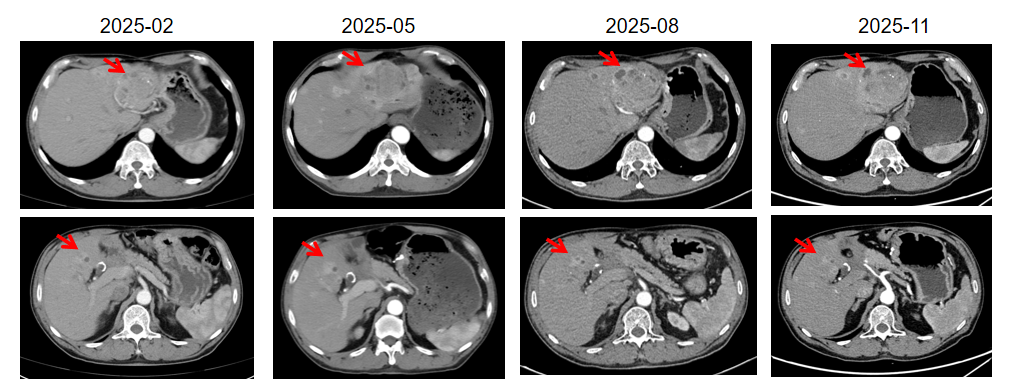

2025年2月PET-CT显示肝转移灶数量及摄取水平较前明显增加。患者随机进入临床研究对照组,开始醋酸奥曲肽微球60 mg q4w。至最新随访(2025年11月)疗效评估为SD。